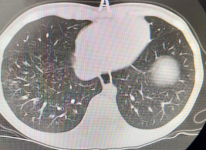

在常见病多发病诊疗基础上,对呼吸系统疑难危重者的诊疗也有独到的优势:重症肺炎的介入治疗(包括盥洗;介入手术取塑性支气管束挽救几近闭塞气管获得再通;利用电切球囊扩张二氧化碳冷冻技术挽救坏死陷闭的气管支气管),支气管异物的取出(包括超过4周的异物造成局部肉芽组织增生、桥联等的诊疗),肺不张的介入治疗可挽救不张的肺叶,降低肺叶切除的风险。支气管扩张症患者定期气道盥洗可改善支扩患儿的生活质量及缺氧情况。已开展气管镜内膜刷检及活检,对EBTB(支气管内膜结核)的诊断,后期可进行局部治疗(包括局部予以异烟肼滴注、钳夹干酪病灶促进病灶恢复等)。随着呼吸专业科研水平提高,对于哮喘支气管哮喘诊断及治疗获得满意的临床疗效,根据炎症介质、哮喘易感基因、哮喘个体化给药基因检测指导临床精准用药、肺功能评估一系列方法的选择,提高了哮喘的诊疗水平。随着二代测序(全外显)的开展,呼吸系统单基因遗传病(囊性纤维化、PCD等)的诊断率逐渐提高,同时呼吸系统病原学的宏基因检测越来越多的应用于临床,减少及避免的抗生素的不合理应用,做到精准诊断精准治疗。

以下为呼吸专业典型病例分享:

图片2:气管狭窄后电切、球囊扩张、二氧化碳冷冻治疗